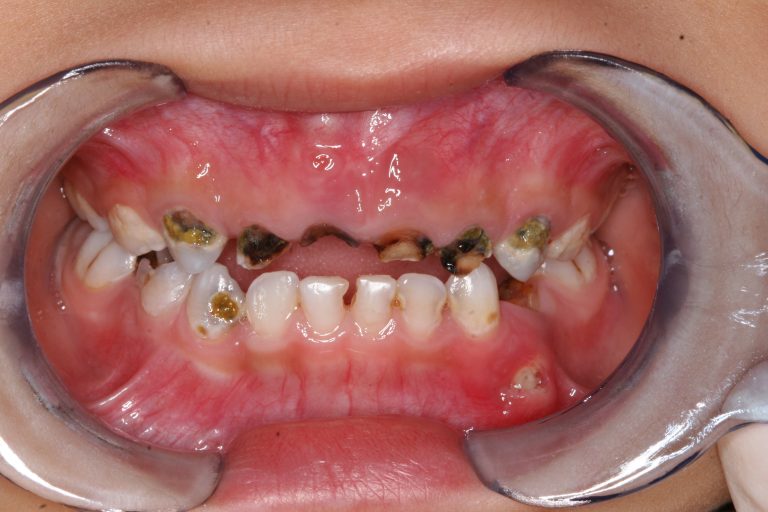

↑ 一名患有嚴重蛀牙的兒童口腔狀況,上排門牙及臼齒已被嚴重蛀壞。

蛀牙對孩子的生活、成長及發展都有相當顯著的影響。小朋友患有蛀牙會感到不適、痛楚;蛀牙是由細菌引起的,嚴重的話,細菌會侵入到牙髓,形成牙瘡。牙列受損,亦對兒童的營養吸收及儀容有負面影響,關係到孩子的發育及整體健康。